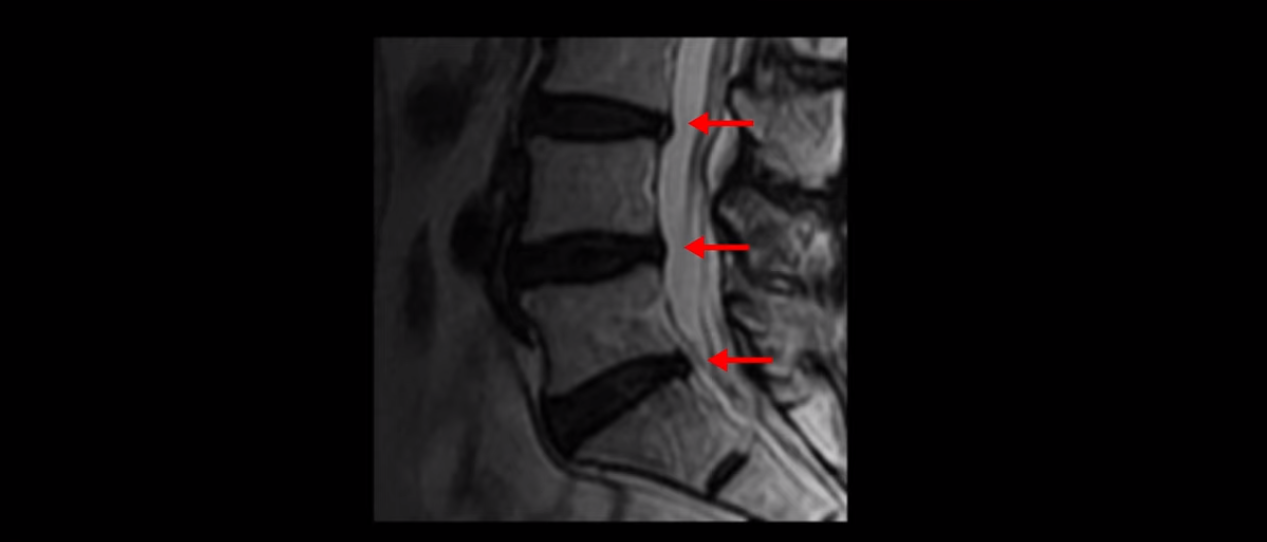

이분 MRI를 보시면 허리 세 마디가 퇴행은 있으나

척추관도 3번 4번

4번 5번

5번 1번

전부 다 충분히 넓고 왼쪽 다리 쪽으로 신경이 나가는 추간공도 전부 다 충분히 넓은 상태입니다.

신경이 눌려 보이지 않는 겁니다. 그러니까 수술 후 MRI를 보고 모든 병원이 전부 다 ‘수술은 잘돼 있다’, ‘아무것도 해줄 게 없다’ 그냥 기다리라고만 얘기했다고 합니다. 신경외과, 정형외과, 재활의학과가 서로 다른 과로 전과시키면서 다들 아무것도 해줄 게 없다고 하니 희망을 잃은 상태였다고 했습니다.